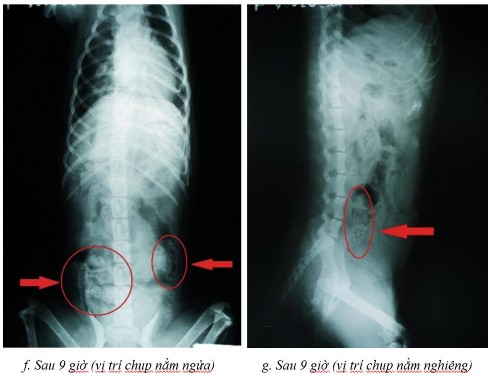

Một số dữ liệu đánh giá sự dịch chuyển in vivo trong đường tiêu hóa chó bằng phương pháp hình ảnh x-quang

Phụ lục 5.1. Hình ảnh X-quang chó 2 ở thời điểm (a) sau 2 giờ ở vị trí nằm nghiêng, (b) sau 4 giờ ở vị trí nằm ngửa, (c) sau 4 giờ ở vị trí nằm nghiêng, (d) sau 7 giờ ở vị trí nằm ngửa, (e) sau 7 giờ ở vị trí nằm nghiêng, (f) sau 9 giờ ở vị trí nằm ngửa, (g) sau 9 giờ ở vị trí nằm nghiêng, (h) sau 11 giờ ở vị trí nằm ngửa và (i) sau 11 giờ ở vị trí nằm nghiêng